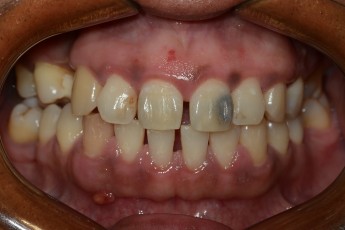

Before

After